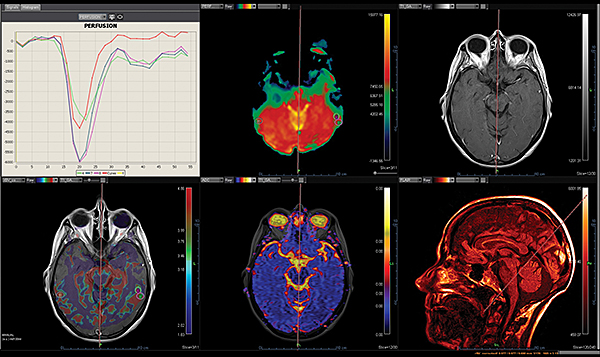

Перфузія DSC Perfusion

Додаток DSC Perfusion обчислює оптимізовані параметричні карти (rBV, rBF, TTP, MTT, TMAX, tMIP) із сирої перфузійної серії та забезпечує алгоритм для корекції ефектів розповсюдження контрастної речовини, обчислюючи карту проникності. Ця програма підтримує нерегулярний вибір часу та складається з наступних модулів: автоматична або ручна обробка arterial input function (функції артеріального наповнення), автоматична сегментація фону, чотири методи деконволюції (sSVD, cSVD, oSVD та байезівський) та алгоритм миттєвої корекції руху.

Дослідження інсульту MR Acute Care Stroke.

Незалежно від важкості невідкладного стану, ці додатки надають радіологам прямий доступ до звіту про інсульт в найкоротші терміни. Ці додатки включають інформацію про кровотік за допомогою унікальних динамічних порогових карт перфузії для візуальної оцінки гіпоперфузованих ділянок та використання методу Байєса для зменшення дози контрасту наполовину для перфузійного дослідження мозку.